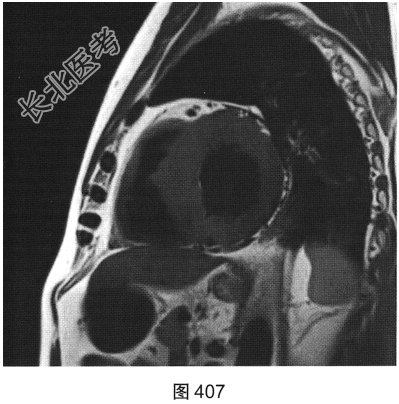

- [材料题] 患者男性,43岁,因“活动后胸痛3年”,外地医院拟诊梗阻性肥厚型心肌病,为明确诊断而转诊本院。

- 简答题3、患者超声心动图检查未能明确诊断,临床申请心脏磁共振检查,如图404~图408所示。患者心脏磁共振检查的异常征象有?